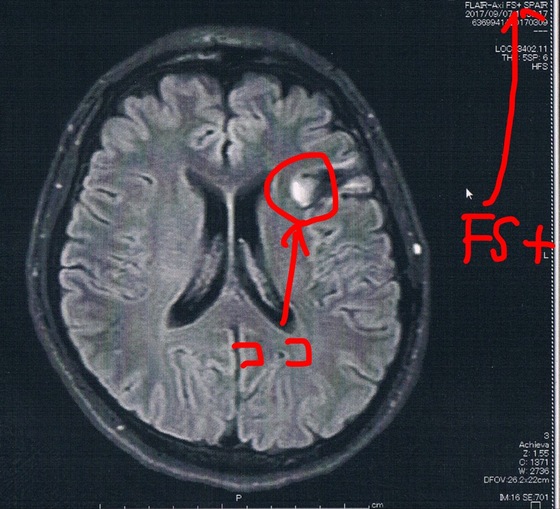

前回2017/9/7(手術後39ヶ月)のMRI画像